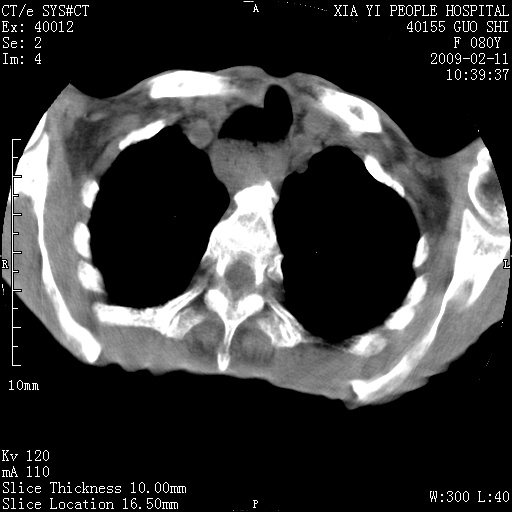

以下是引用随光逐影在2009-2-16 16:34:00的发言:[br]1)考虑右前纵隔皮样囊肿。2)双侧少量胸腔积液。

以下是引用zjzjr在2009-2-16 17:30:00的发言:[br]支持囊性畸胎瘤 双侧少量胸腔积液。